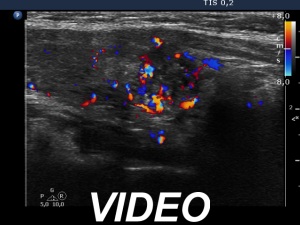

Ultrasonography. The thyroid was minimally hypoechoic and had more hypoechoic areas. There was a more hypoechoic nodule in the lower pole of the right lobe. The lesion has irregular, lobulated margins and numerous microcalcifications. A few microcalcification were found outside the core of the tumor. The intranodular vascularization was irregularly increased.